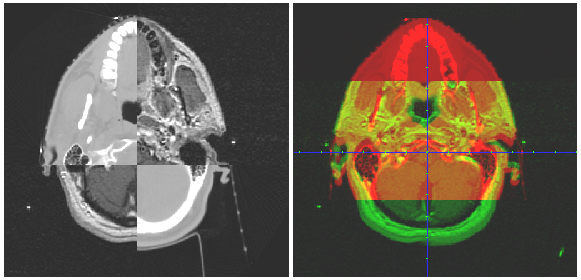

Fig. 1. Illustration of two common means of image alignment based on 2D planar views

(Only one of the axial slices is shown, and the sagittal and coronal series are not shown).

several means to achieve the visual alignment verification: (1) the chess-box display of two

images in alternate boxes; (2) the simultaneous display of two mono-coloured images; and

(3) the superimposed display of the two images with an adjustable weighting factor. Fig. 1

illustrates the first two of the three basic visualization methods.